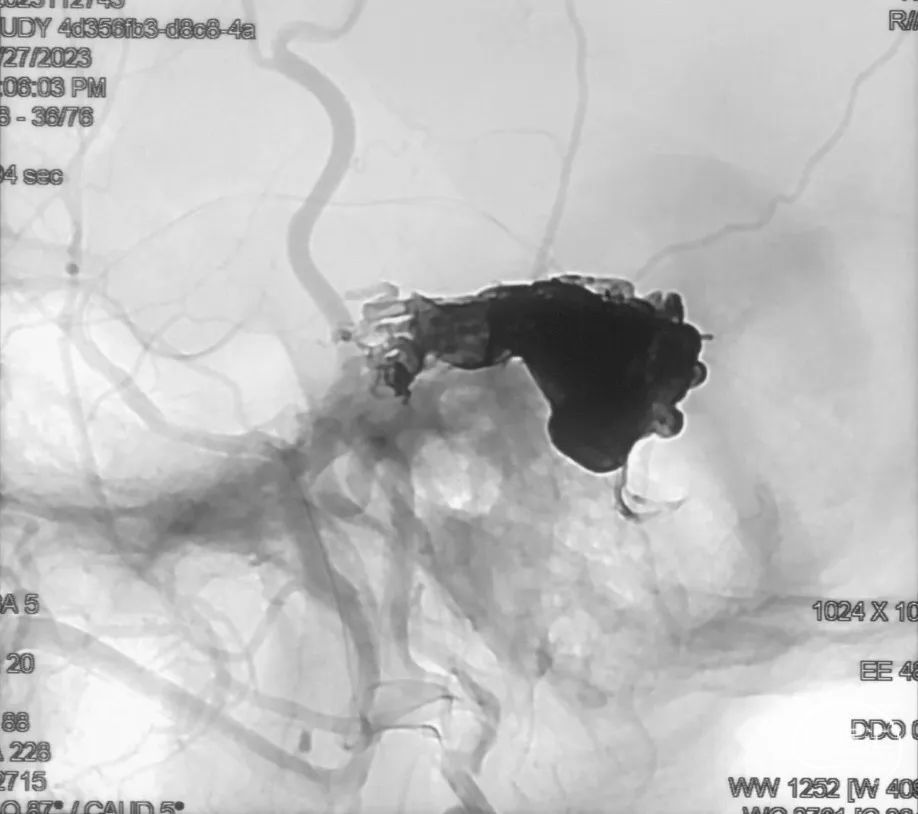

治疗结果

双侧颈外、颈内动脉正侧位造影瘘口均不显影

双侧椎动脉造影未见瘘口显影,可见广泛皮层静脉瘀滞

Onyx胶铸型显示瘘口形态。

术后药物指导

1、依诺肝素钠 4000U q12h*3d

患者后循环造影可见皮层静脉广泛淤滞样改变,遂予以抗凝药物治疗。